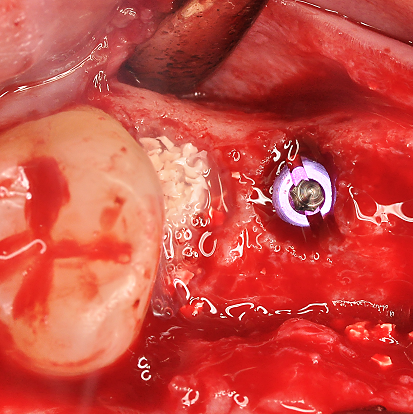

Treatment of a double root fracture in the aesthetic zone with cerabone® – Dr. J. M. Abarca

47 years old patient referred by another dentist after suffering a fall while fishing